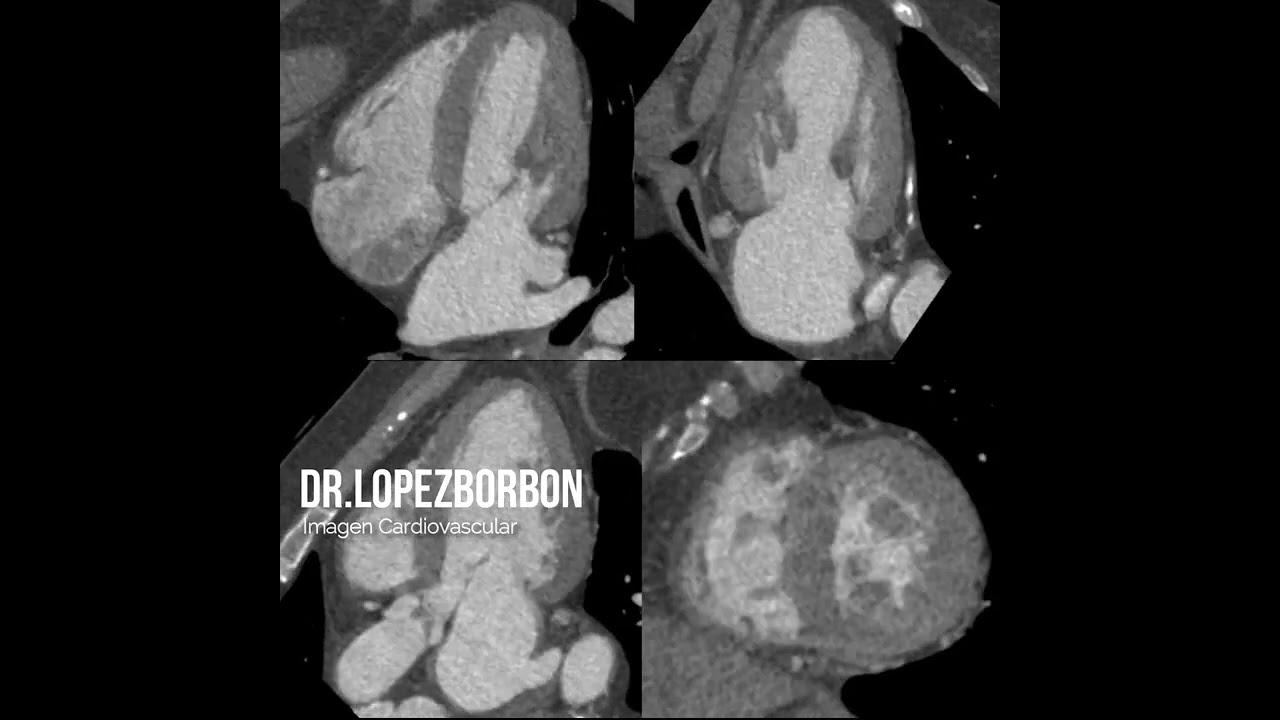

Cardiólogo Clínico y Ecocardiografista con alta especialidad en Resonancia Magnética Cardíaca y Angiotomografía Coronaria. Experiencia en diagnóstico preciso de enfermedades cardiovasculares mediante ecocardiografía convencional, ecocardiografía transesofágica, estudios de estrés físico y farmacológico, RMC y ATC. Formación en Cardiología Clínica en el Centro Médico Nacional del Noroeste (Ciudad Obregón), alta especialidad en Ecocardiografía de Adultos en el Hospital de Cardiología #34 (IMSS, Monterrey) y alta especialidad en RMC y ATC en el Instituto Nacional de Cardiología Ignacio Chávez (CDMX). Comprometido con una atención cercana, amigable y personalizada para cuidar tu salud cardiovascular de manera integral.

Alta especialidad en resonancia magnética cardiaca y angiotomografía, Instituto nacional de cardiología CDMX.